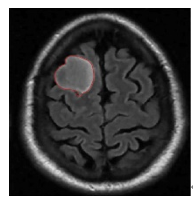

5.4 Results on brain MRI images

To achieve accurate segmentation of medical images, we have carefully tuned the parameters α, λ, and μ, which play a critical role in the performance of the DRLSE algorithm. These parameters control key aspects of the level set evolution, such as the smoothness of the contour (α), the fitting to the object boundaries (λ), and the regularization of the level set function (μ).

Using an empirical approach, we iteratively adjusted these values to obtain the best segmentation results for the images shown in Figure 10. Specifically, for brain MRIs, we found that setting α=0.5, λ=6, and μ=0.02 provided optimal segmentation results. These values effectively balance the trade-off between contour smoothness and accuracy in detecting object boundaries.

The segmentation process required several iterations to refine these parameters, highlighting the importance of adapting them to the specific characteristics of the images being analyzed. The results confirm the robustness of the DRLSE algorithm in delimiting structures in medical images.

Figure 10. Segmentation result. with the DRLSE algorithm